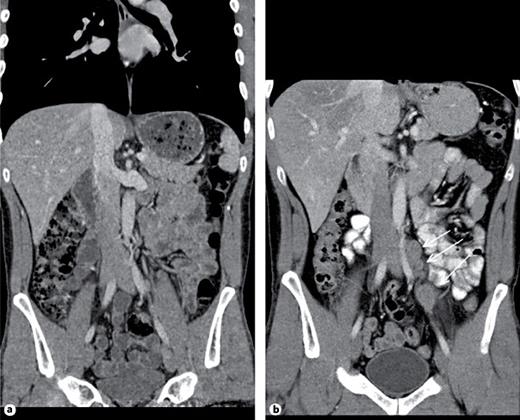

4th patient: this 37-year-old patient had left-sided orchiectomy for a presumed occult germ cell tumour. Histologically, only germ cell neoplasia in situ (TNM: pTis) was found in the specimen. CT revealed a 1.8 cm lymphadenopathy in the para-aortal template. All of the classical serum tumour markers were negative. As histopathologically no invasive GCT was found in the left orchiectomy specimen, the lymphadenopathy was considered unspecific corresponding to a CS1. Accordingly, the patient was put on a surveillance schedule. Four months later, the lymphadenopathy had slightly increased (Fig. 3). Therefore, a laparoscopic lymphadenectomy was performed. Histologically, the specimen revealed a pure seminomatous metastasis. The patient received 3 cycles of BEP chemotherapy subsequently. Before orchiectomy, the miR371a-3p serum level was RQ = 74.4 and it was found to decrease to RQ = 20.4 three days postoperatively, thus clearly lying in the supra-normal range. Prior to lymphadenectomy, the level had increased to RQ = 58.5 and it dropped to RQ = 0.0 after surgical excision of the node to remain there during the later course.

Abdominal CT of patient #4, 4 months after orchiectomy: para-aortal lymphadenopathy. Laparoscopic excision revealed seminoma.